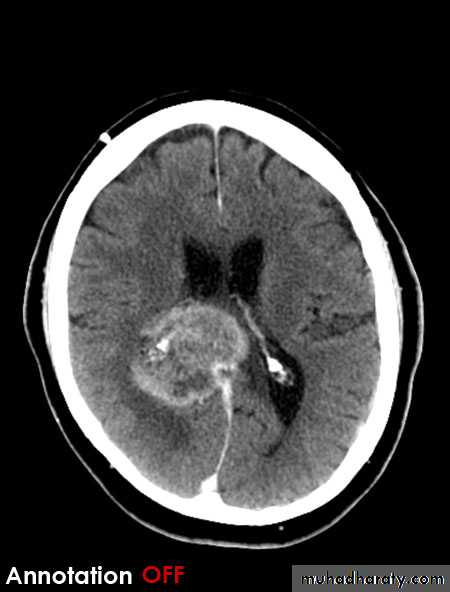

Haemangioblastoma

Arise from per vascular pericyte

GII to III in their malignancy

Age between 30 -65 Y , represent 10 % of PFT

Intra axial t. arise from the cerebellum , brain stem ,spinal cord

CT finding , as smooth walled cystic lesion with enhancing mural nodule rarely calcified .